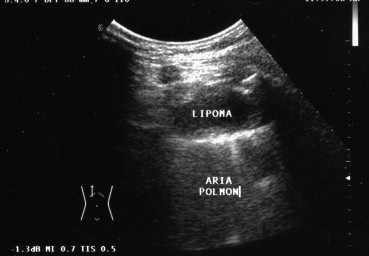

Uniformly anechoic pulmonary lesions, usually well circumscribed, may represent cysts (congenital, bronchogenic, parasitic, or pleural) or, more rarely, pulmonary infarcts. Lipomas, which are benign tumors, appear on US as localized nodules that are hypoechoic or anechoic (Fig. 7). The presence of echoes within a hypoechoic–anechoic cyst is indicative of a “complex” lesion, such as an abscess, a hematoma, a necrotic neoplasm, or a multivesicular hydatid cyst [17] (Fig. 8). Pulmonary abscesses appear as circumscribed, collections of corpuscular fluid. They can be detected easily with US when they are located in the peripheral regions of the lung, close to the parietal pleura, or associated with pleural adhesions [18].

Fig. 7.

Pulmonary lipoma appears on US as a localized hypo-anechoic nodule.